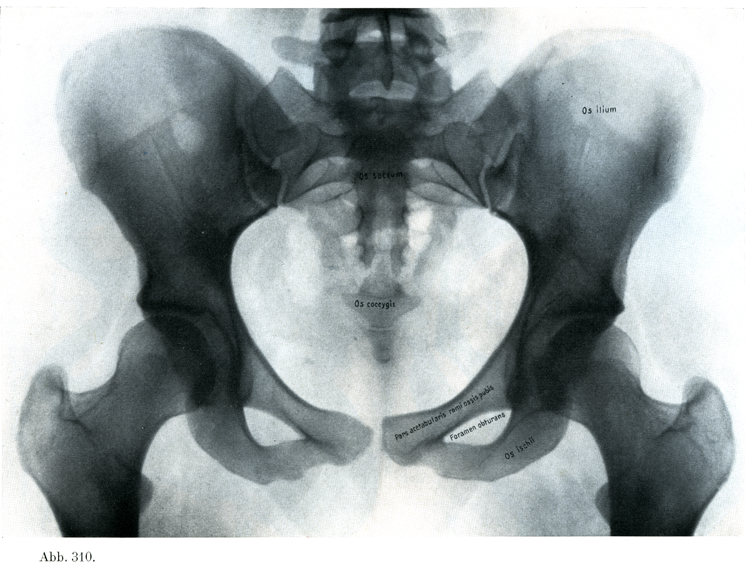

[図310]女の骨盤 20才の少女の骨盤のレントゲン写真, 腹背照射.